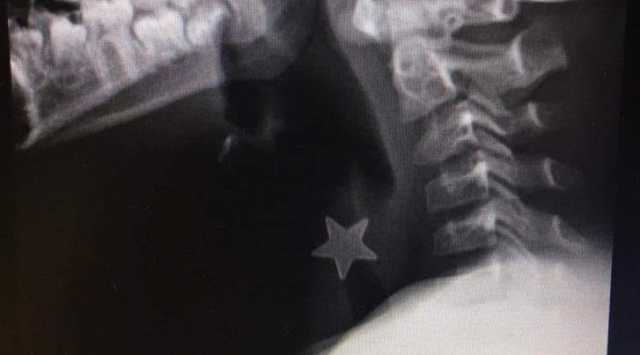

Italia e mondo Ingoia una stella di metallo e rischia di morire: bimbo di 8 anni salvato al Niguarda Redazione 19 Giugno 2020 Italia e mondo Il farmacologo Remuzzi: "Basta paure, molti nuovi positivi sono meno contagiosi" Redazione 19 Giugno 2020 Italia e mondo Primi ricoverati per Covid in Italia, i turisti cinesi donano 40mila euro allo Spallanzani Redazione 18 Giugno 2020 Pagina 1273 di 1946 Indietro1268126912701271127212731274127512761277Avanti Altre in Italia e mondoItalia e mondoAlto Adige, morto il bambino caduto in piscina: era appena stata inaugurataItalia e mondoAntitrust sanziona Apple per 98 milioni per abuso di posizione dominanteItalia e mondoCaso Signorini, denunciato Fabrizio Corona per "Revenge porn"Italia e mondoFamiglia nel bosco, respinto il ricorso della coppia: i bambini restano in comunitàItalia e mondoTaranto, picchia la compagna davanti ai figli e le rompe telefono e occhiali: arrestato Italia e mondoLa premier Meloni: "I nostri soldati non andranno in Ucraina, non abbandoniamo Kiev" Altre notiziePrimo PianoOrrore a Oliena, uccide a calci il cane della sua famiglia davanti al fratello minorenne: denunciato In SardegnaOss in Sardegna, il sistema assistenziale nell'Isola è "al collasso": la denunciaIn SardegnaAou di Cagliari, la storia di Mattia: il neonato più piccolo nato in Sardegna, ha pesato 398 grammiIn SardegnaBabbo Natale a cavallo nel ricordo di Annalisa: solidarietà e speranza per i pazienti oncologici di SassariPrimo PianoControlli a tappeto prima di Natale: 100 chili di pescato sequestrati in SardegnaPrimo PianoPrende a calci il cane e lo uccide, ma lo vedono i fratelli: denunciato a Oliena Home Canali Intrattenimento Fucked News Cinedelirium YouTalk È Qui La Festa? Calcio al mercato Your Voice Contro TG Cagliari Social Arena Opinioni I Care Turismo Sardegna fuori rotta Sardegna 360° Supramonte Seaside Sardinia is different Video del giorno Musica Dai Comuni In Sardegna Italia e mondo Sport WSC 2021 Boxing: match Italia - Moldavia - Romania Scienza e tecnologia Culture StorieEventi Sa Sartiglia Cabudanne de sos Poetas Centenario PSdAz Marina Cafè Noir Premio Letterario Dessì Sant'Efisio Sant'Antioco Martire Cuncambias ON AIR Mediazione Internazionale Diamoci una Scossa! Signal Reload Archeologika 2021 V-art Festival Erbafoglio 2021 WSC 2021 Festival Oltre il senso Miss Italia 2023 TV dei Comuni Lingua Sarda Novas #7DiesWeb series Lost in Sardinia Posidonia Team ARTExhibition Imprentas - Oindì News TG Chi Siamo Contatti Privacy policy Youtg.NET Cookie policy